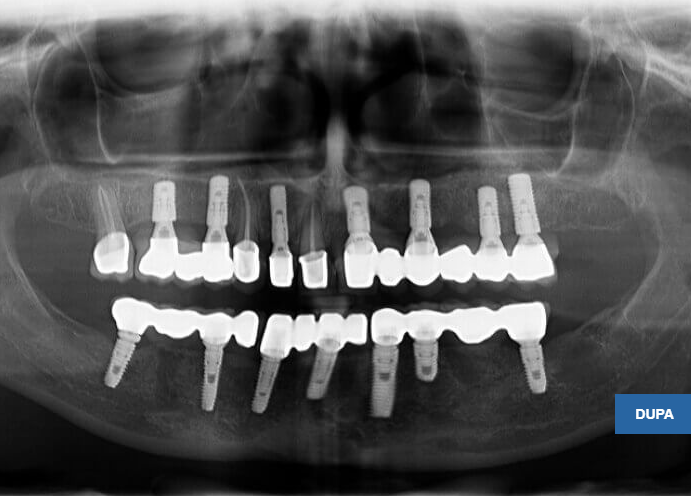

Pacienta în vârstă de 46 ani se prezintă în clinică având edentație uniterminală bimaxilară (maxilar 1 modificare, mandibulă 4 modificari) cu parodontopatie marginală cronică profundă, dinții prezentând mobilitate grad 3, o proteză mobilă parțial acrilică incorect adaptată campului edentat cauzând inflamația mucoaselor pe care se sprijinea, restaurări protetice fixe metalo-ceramice incorect adaptate, unele fixate provizoriu pe bonturi fracturate, reacții periapicale.